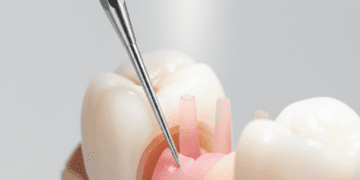

Dentina: Localizada logo abaixo do esmalte e do cemento, a dentina é uma camada menos mineralizada e mais porosa, composta por túbulos dentinários que permitem a condução de estímulos ao interior do dente. É responsável por fornecer suporte estrutural ao esmalte e transmitir sensações dolorosas ou térmicas.

Polpa dentária: O tecido mais interno do dente, repleto de nervos, vasos sanguíneos e células conjuntivas. A polpa é vital para a nutrição e sensibilidade do dente, estando localizada na câmara pulpar da coroa e nos canais radiculares na raiz.